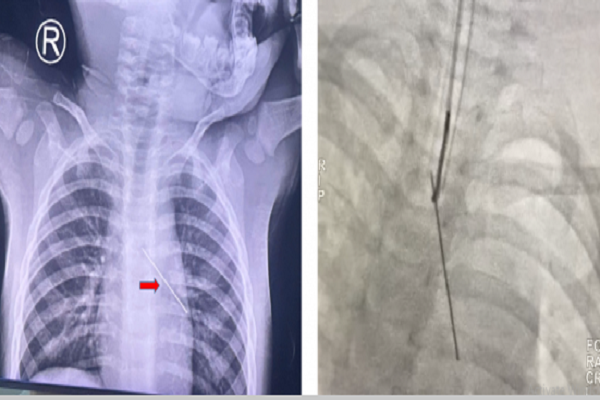

Hình ảnh X-quang cho thấy, dị vật ở phế quản góc trái được dùng dụng cụ "tim mạch" để can thiệp "hô hấp", lấy dị vật đường thở là cây kim cúc

Tại bệnh viện địa phương, phim X-quang ghi nhận một thanh kim loại nằm gọn trong đường thở, buộc các bác sĩ phải chuyển gấp bệnh nhi lên tuyến trên.

Nội soi đường thở cho thấy tình huống đáng lo ngại: chiếc kim cúc sắc nhọn nằm ở phế quản gốc trái, đầu nhọn hướng ngược lên vùng carina (ngã ba khí – phế quản) và găm sâu vào thành sau phế quản. Mọi nỗ lực gắp dị vật bằng các dụng cụ thông thường như kiềm cá sấu đều thất bại do nguy cơ gây rách, tổn thương nghiêm trọng đường thở.

Với độ chính xác cao, vòng dây snare đã ôm trọn mũi kim và thu gọn dị vật vào trong lòng ống nội khí quản. Sau đó, các bác sĩ tiến hành rút đồng thời cả ống nội khí quản cùng chiếc kim ra ngoài. Cách làm này giúp triệt tiêu hoàn toàn nguy cơ mũi kim gây trầy xước đường thở trong quá trình lấy dị vật.